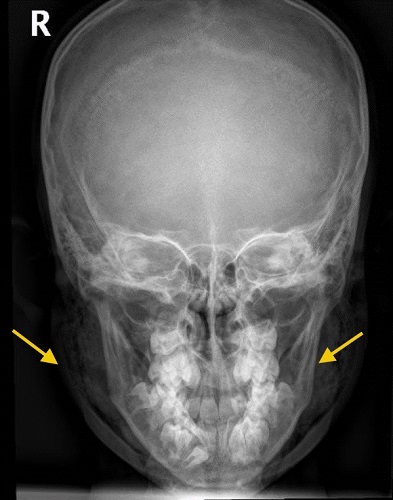

Se realiza una radiografía (Fig. 1), donde se objetiva presencia de aire en ambas glándulas parótidas (compatible con neumoparótida bilateral), con extensión del enfisema subcutáneo a región laterocervical bilateral, sin signos de neumotórax ni neumomediastino. Las estructuras óseas no muestran alteraciones.

| Figura 1. Signos de neumoparótida bilateral con extensión del enfisema subcutáneo a región laterocervical bilateral |